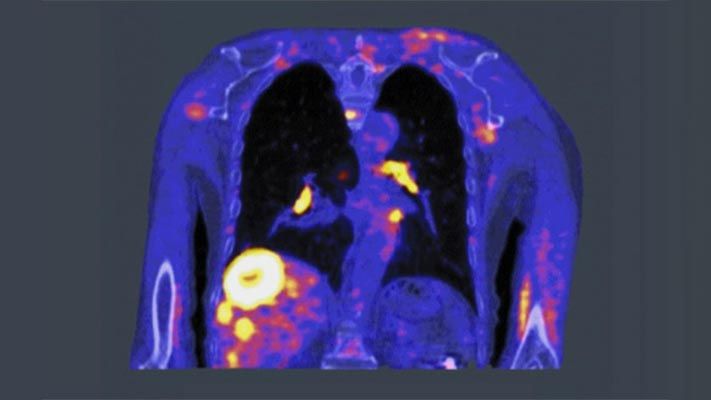

Radiotherapy uses high doses of radiation to kill cancer cells and shrink tumors. It’s performed after imaging scans such as positron emission tomography (PET), magnetic resonance imaging (MRI), or computed tomography (CT) locate the target tumors. Those images help medical professionals decide where to aim the radiation beam and determine the treatment field. But because the process requires two steps, doctors are forced to add a margin of error around the tumor.

PET scan highlights cancer cells using a small amount of a radioactive drug, called a tracer